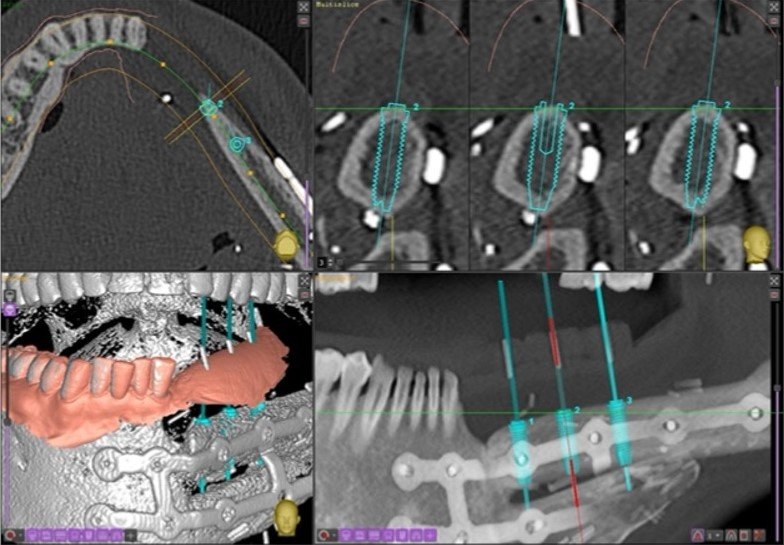

OPG radiograph illustrates Branemark implant fixtures placed in Brisbane by Dr. Darveniza for each of the upper and lower jaws in readiness for All-on-4 Fixed-Removeable implant dentures.

-

The results of the software program designed by a programmer in Belgium with Dr. Darveniza to create Atlantis Abutments of the correct size and shape overlaid inside the diagnostic conventional removeable acrylic resin dentures I made.

After designing the Atlantis titanium abutments with the Belgium programmer via email, the 8 abutments were milled of titanium in Sweden.

The milled abutments with 5 degree tapered walls and a millimetre wide chamfers, and with all 4 abutments being parallel to each other in each arch.

The titanium abutments screwed into the implant fixtures on the lower arch.